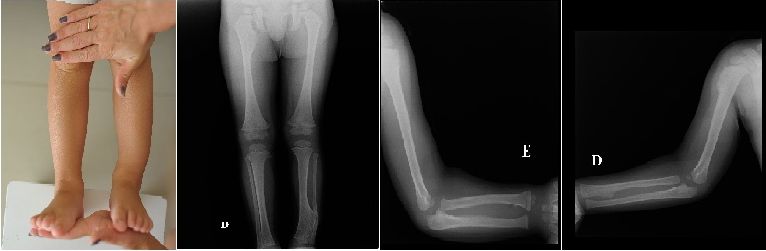

Здравствуйте, уважаемые коллеги!Посоветуйте как поступить при деформации голени у

ребенка.

Ребенку 2 года 8 месяцев. Около полугода назад появилась деформация нижней трети левой

голени. Сделали рентгенограммы. У матери ребенка так же экзостозы в верхней трети

большеберцовой кости, ребер. Что можно предпринять при такой деформации голени?